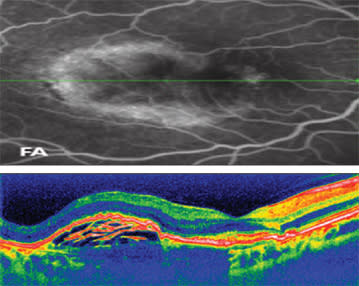

"Conventional OCT indicated the presence of early new vessel growth in AMD in a more indirect fashion, with changes such as cystoid retinal edema and the accumulation of subretinal fluid, which are the result of underlying CNV pathology. With Fourier-domain OCT however, we now can see more detailed characteristics of CNV activity," explains Dr. Mehta, who uses the RTVue-100. "With twice the resolution of standard OCT, spectral domain gives us excellent images of the choroid-RPE complex. Topographical subanalysis of this region will assist us in earlier diagnosis and treatment of CNV, before overlying retinal changes occur."

According to practitioners, image resolution is vastly better with the new technology. "I get the exact information I need for diagnosis with excellent resolution," says Dr. Huang, who uses the RTVue-100. "I can get a broad view of the lesions with the RPE elevation and retinal thickness maps, and home in on the details of the choroidal neovascular membrane with high-definition cross-section images that can be lined up with fluorescein angiography.